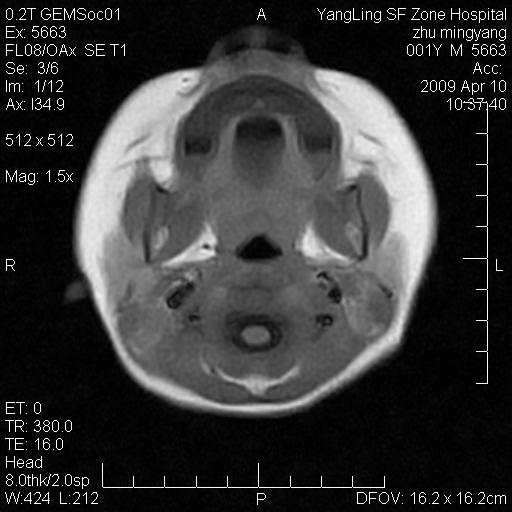

患者:1岁半,两天前外伤收住我院,ct检查小脑占位

考虑星形细胞瘤,建议增强

髓母细胞瘤或血管母细胞瘤,增强后可以鉴别;影像资料见 <。鱼博浪老师的《中枢神经系统ct与mr鉴别诊断》 小脑部肿瘤章节。

髓母细胞瘤或血管母细胞瘤!支持!

支持考虑髓母细胞瘤

考虑----髓母细胞瘤可能性大

考虑髓母细胞瘤或室管膜瘤。

支持髓母细胞瘤。

考虑髓母细胞瘤。

考虑髓母细胞瘤或星形细胞瘤

考虑髓母细胞瘤.

考虑髓母细胞瘤可能性大。

小脑肿瘤.考虑髓母细胞瘤可能.

就病灶部位及临床资料首先考虑髓母.